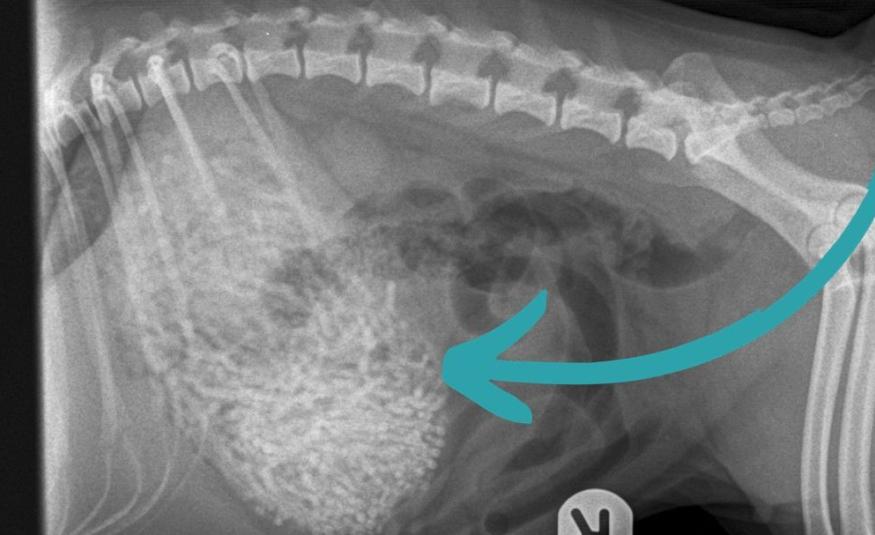

Porodica šokirana onim što su veterinari pronašli u stomaku njihovog psa